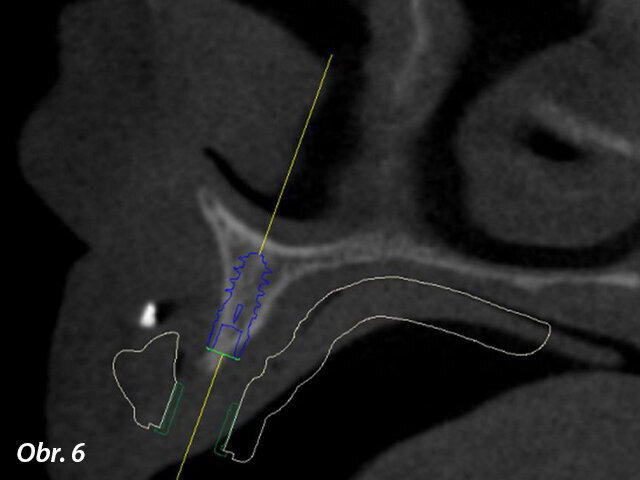

Prostřednictvím softwaru coDiagnostiX jsme zjistili, že je k dispozici dostatek kosti pro zavedení implantátů, kromě dvou oblastí, do nichž bude nutno transplantovat kostní štěp (obr. 5, 6). Bylo naplánováno celkem šest implantátů s adekvátním rozložením po oblouku, které vytvoří podpěru pro žvýkací síly a zabrání jednostranné zátěži (obr. 7). Zavedení implantátů bylo naplánováno za použití chirurgické šablony (obr. 8) a na implantáty měla být hned po chirurgickém zákroku našroubována provizorní náhrada – jednalo se tedy o protokol okamžitého zatížení.